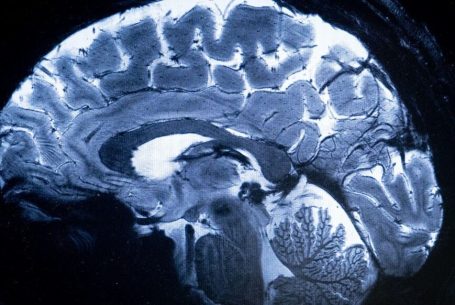

Médical

Voir n’est plus regarder : c’est comprendre la structure du monde cellulaire.

Loin du contraste classique, ϕ explore la richesse interne des tissus.

Elle distingue l’homogène du structuré, le bruit du sens, et redonne au regard médical une dimension topologique : celle de l’information vivante.

Les structures fines, souvent invisibles à l’œil nu, s’y dessinent comme des reliefs entropiques — un paysage du corps, révélé par la mathématique du vivant.